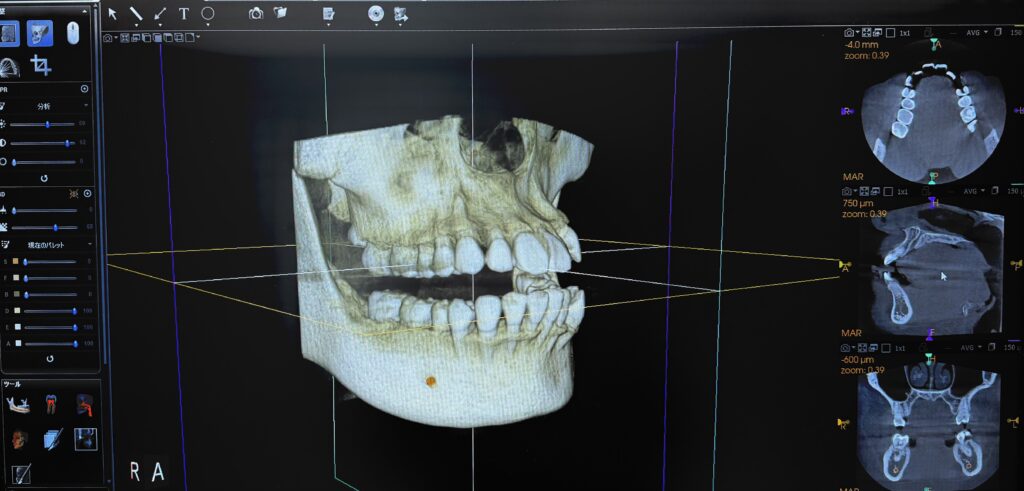

↑歯科用CT(3D)

歯科用CTとは口腔内のレントゲンを立体的(3D)に撮影ができる装置の事です。

3Dのレントゲンを撮影することで、2Dのレントゲンでは確認できない歯の根の形態や病巣の広がり、骨の厚み等を診断が可能になります。